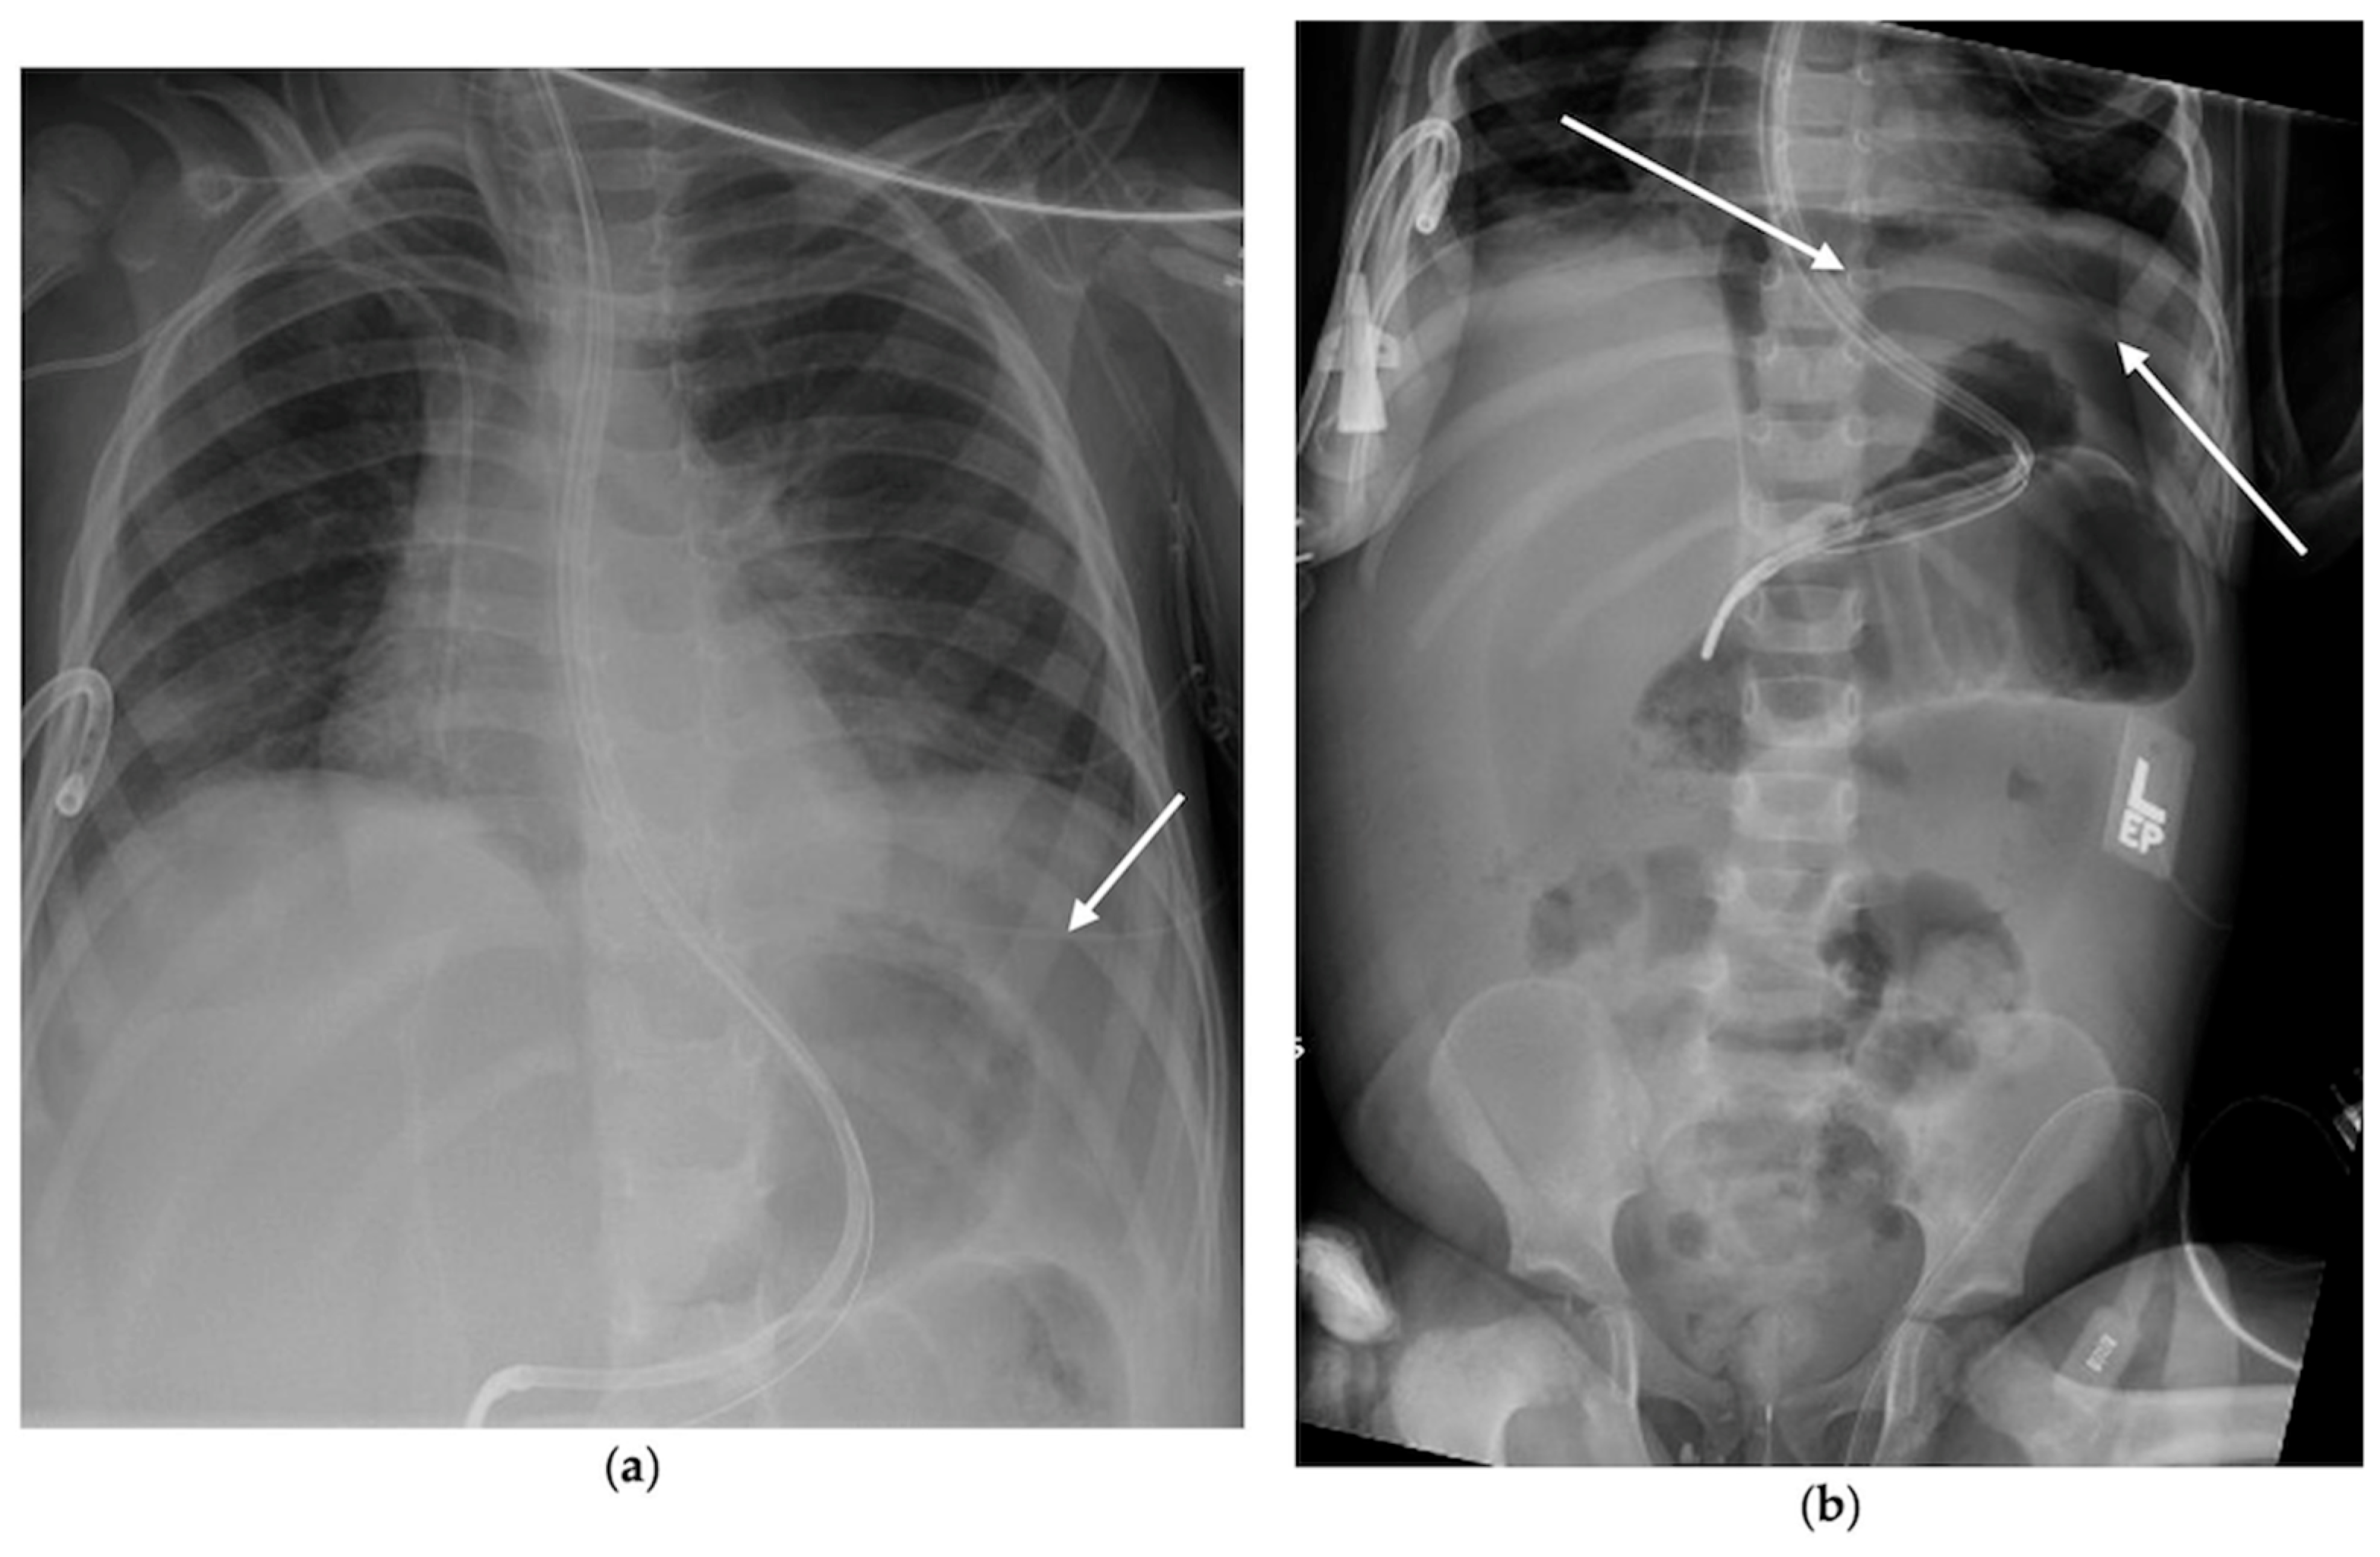

2.1.1. Case 1

2.1.2. Case 2

2.1.3. Case 3